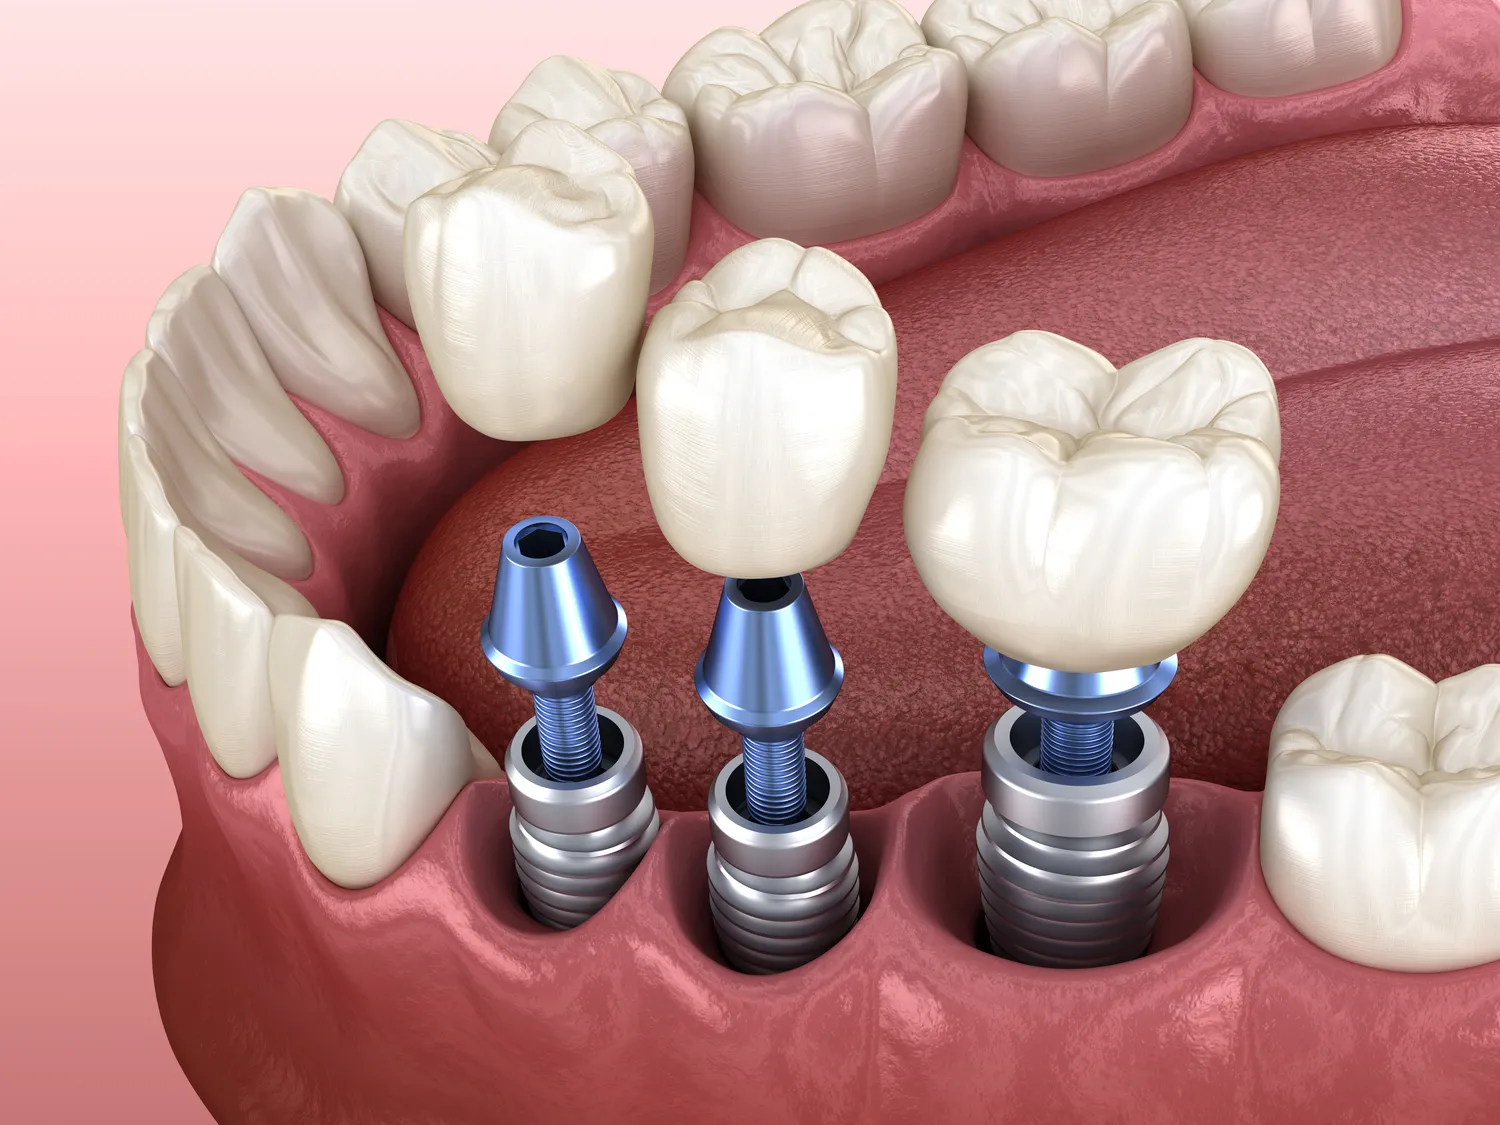

Proces zakupu i wszczepienia implantów zębowych składa się z kilku kluczowych etapów, które wymagają staranności i współpracy między pacjentem a dentystą. Pierwszym krokiem jest konsultacja stomatologiczna, podczas której lekarz ocenia stan zdrowia jamy ustnej pacjenta oraz wykonuje niezbędne badania diagnostyczne, takie jak zdjęcia rentgenowskie czy tomografia komputerowa. Na podstawie tych informacji dentysta podejmuje decyzję o możliwości wszczepienia implantu oraz planuje szczegółowy przebieg leczenia. Następnie przeprowadzany jest zabieg chirurgiczny polegający na umieszczeniu implantu w kości szczęki. Po tym etapie następuje okres gojenia, który trwa zazwyczaj kilka miesięcy; w tym czasie implant integruje się z kością. Po zakończeniu procesu gojenia lekarz wykonuje odbudowę protetyczną, czyli zakłada koronę na wcześniej umieszczony implant. Ważnym elementem tego procesu jest również edukacja pacjenta dotycząca pielęgnacji implantu oraz regularnych wizyt kontrolnych u dentysty.